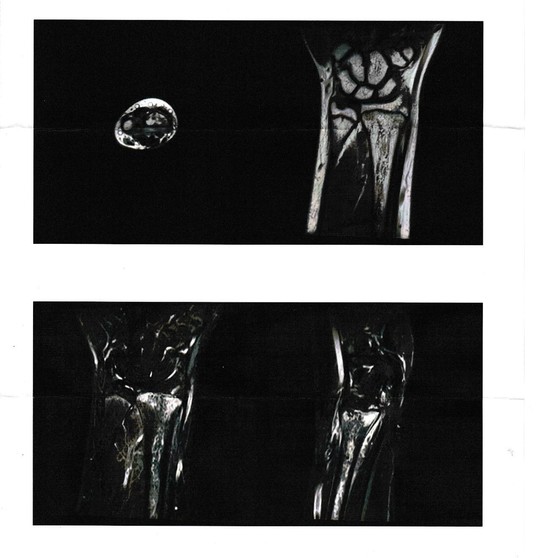

MRI画像

レントゲン・MRI画像上、左橈骨遠位端部の骨折ありと診断。

整形外科にて前腕〜手部のギプス固定を施行。